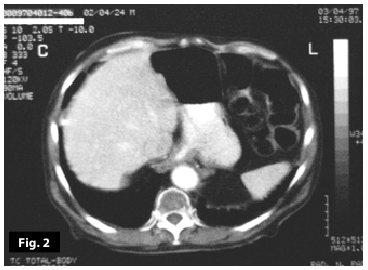

Figure9-10